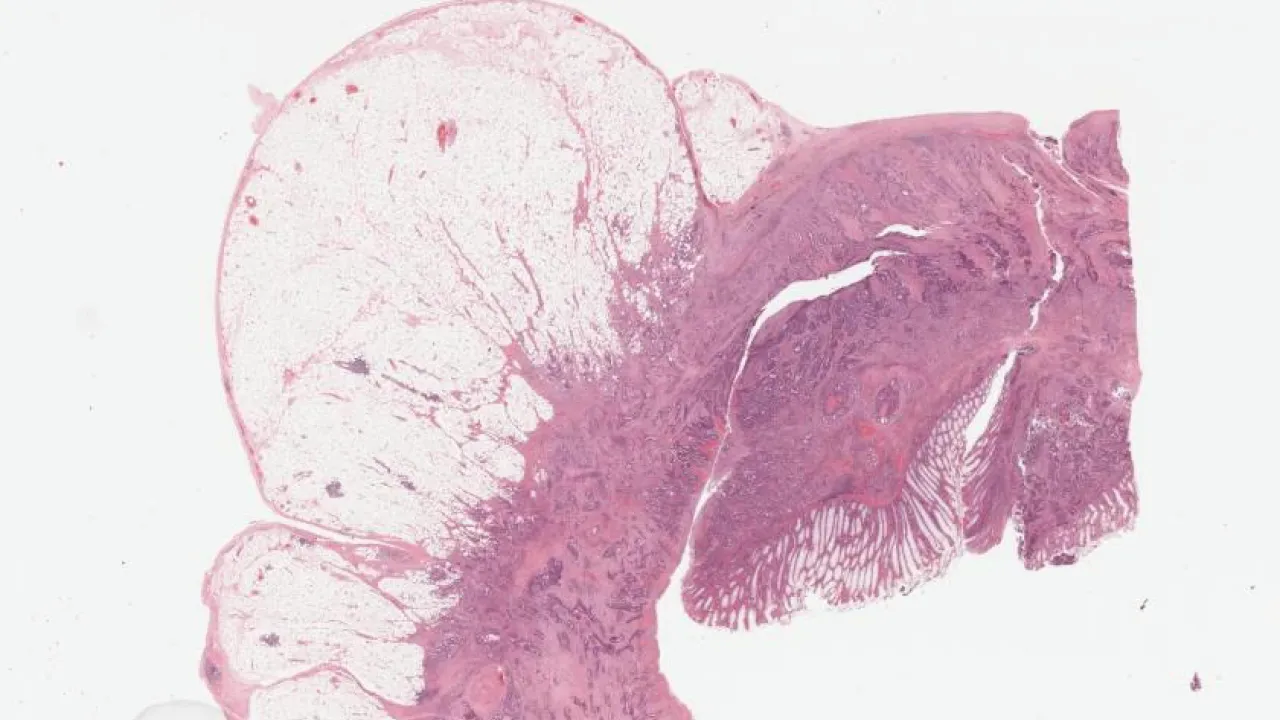

Bladder, High grade papillary urothelial carcinoma